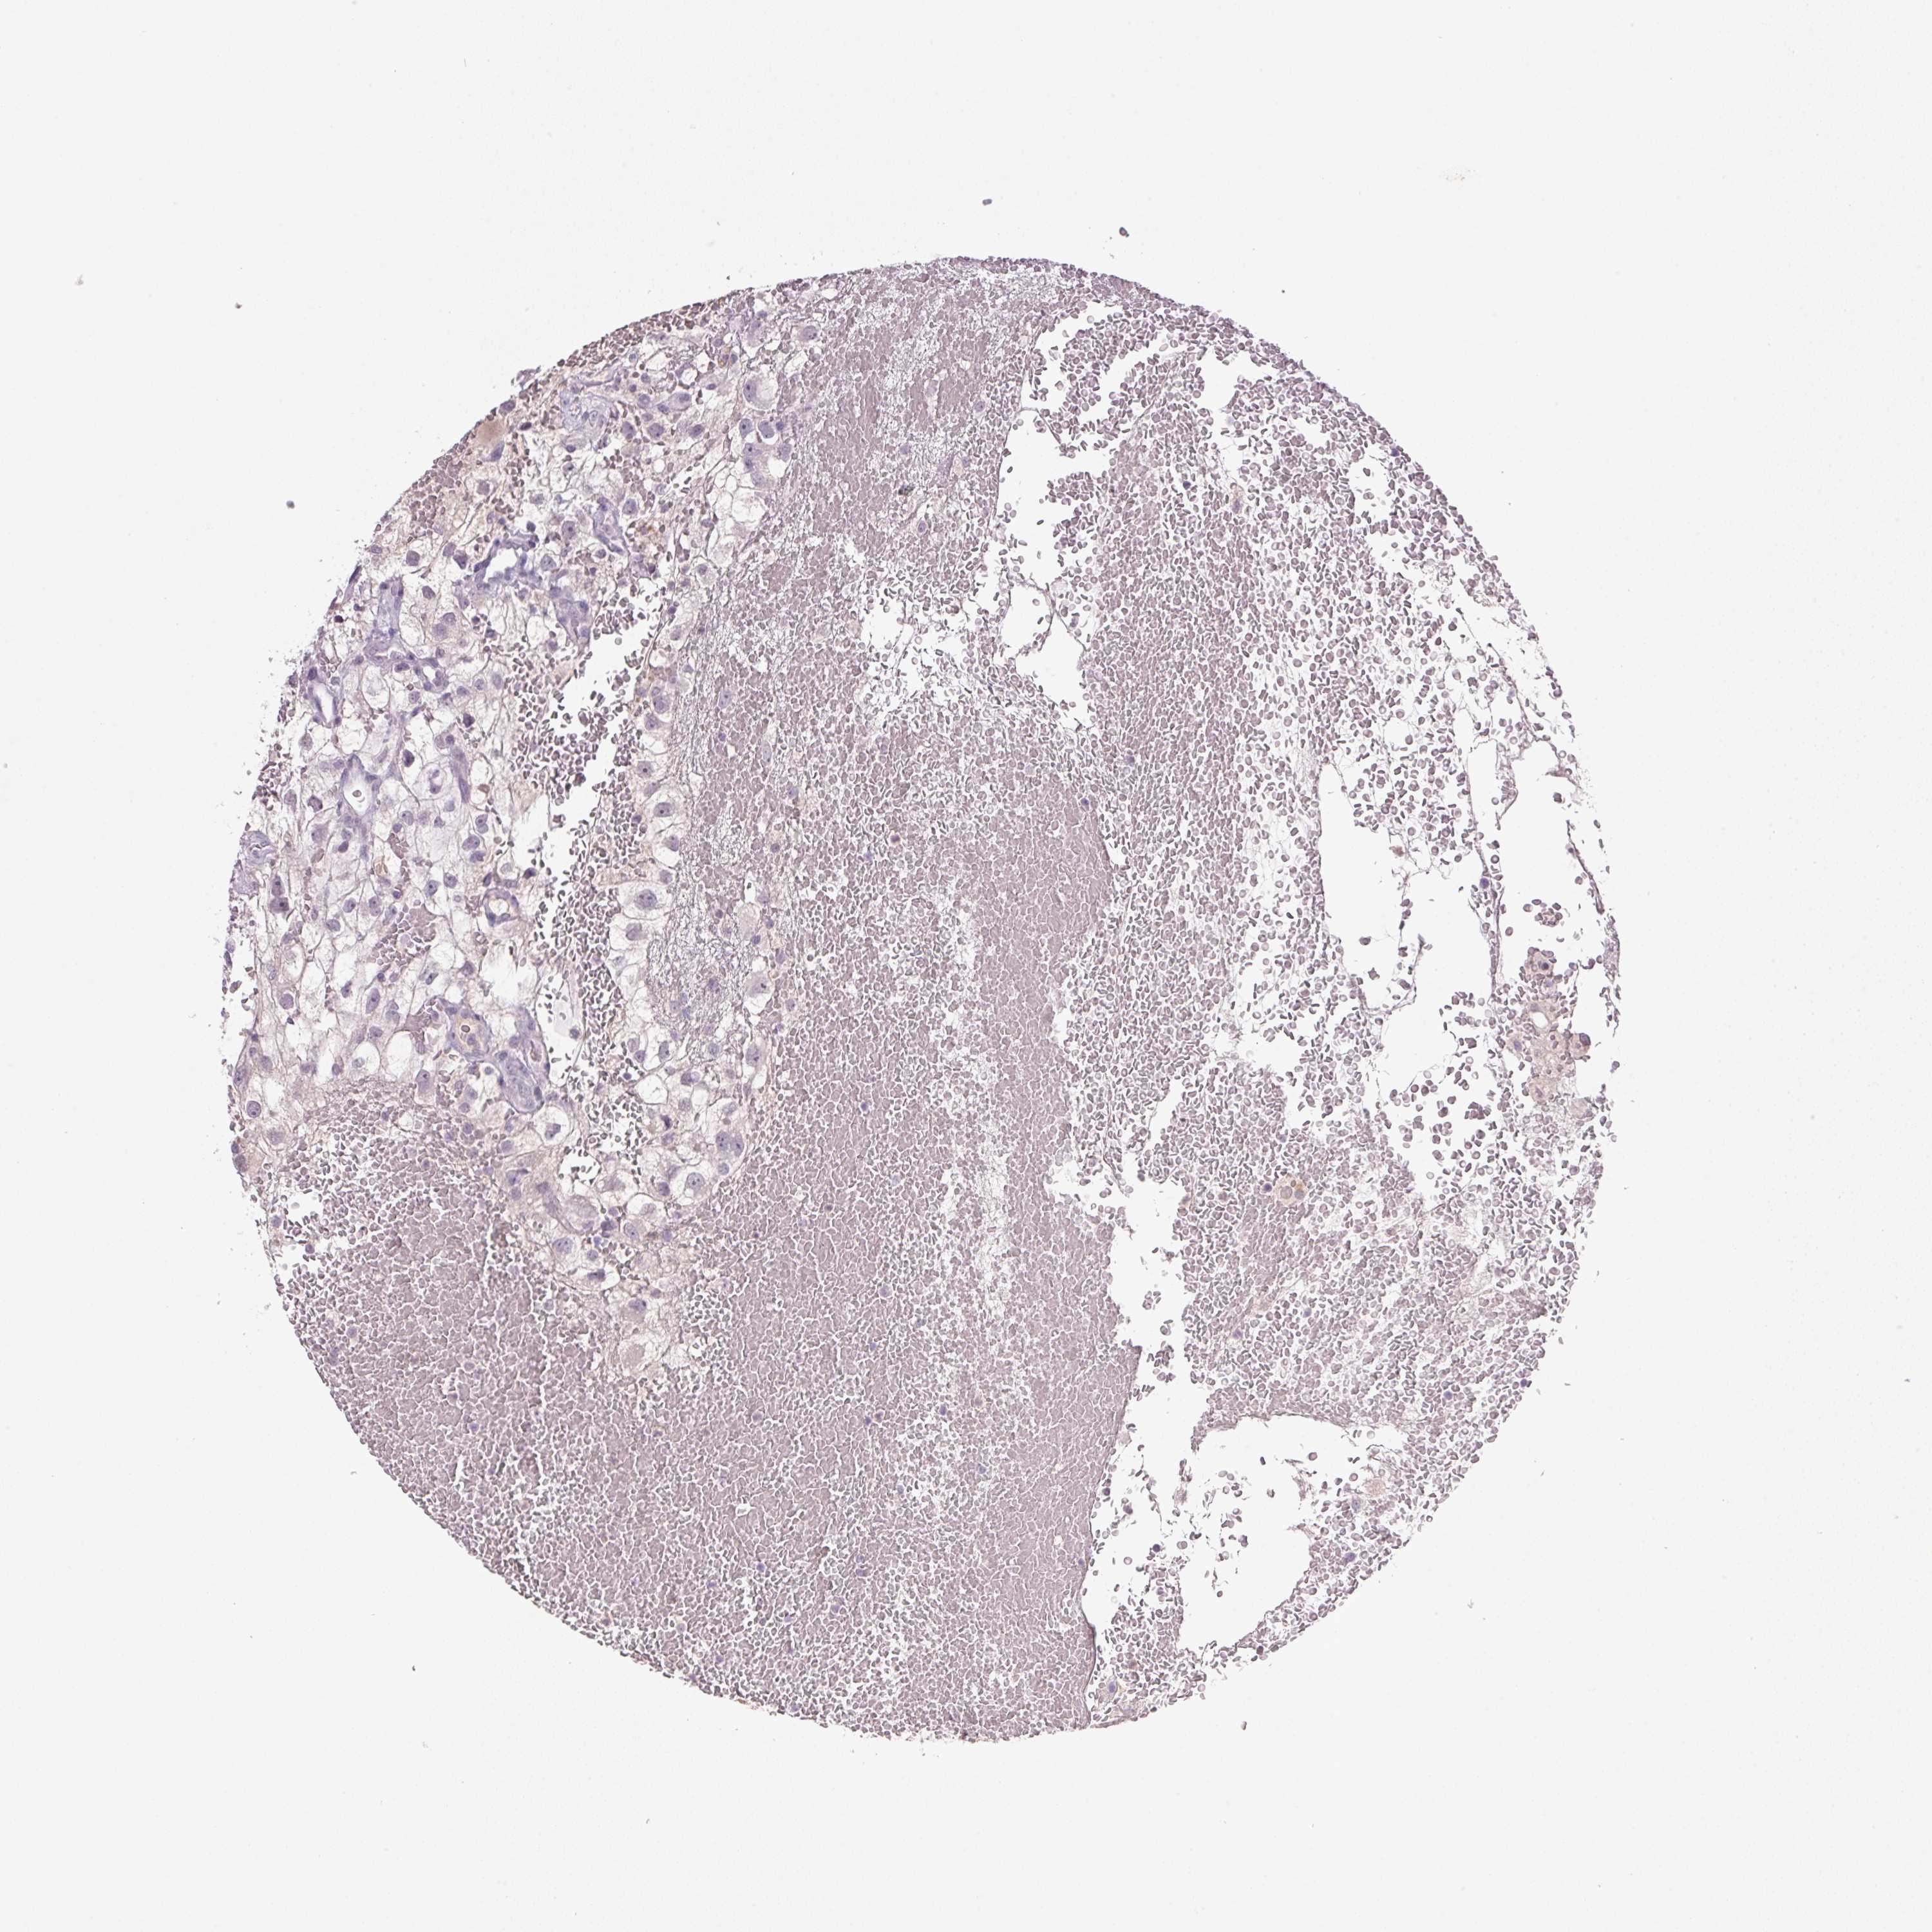

TCGA RNA samplesi

RNA-seq data is reported as average FPKM (number Fragments Per Kilobase of exon per Million reads), generated by the The Cancer Genome Atlas (TCGA) .

Normal distribution across the dataset is visualized with box plots, shown as median and 25th and 75th percentiles. Points are displayed as outliers if they are above or below 1.5 times the interquartile range. FPKM values of the individual samples are presented next to the box plot.

Average pTPM 0.0

Number of samples 100